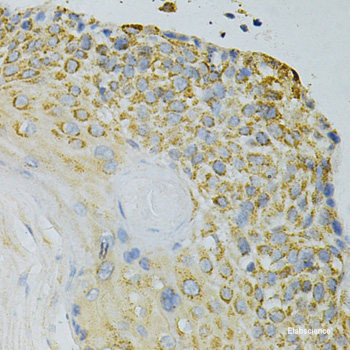

Product information "Anti-GPX4"

The protein encoded by this gene belongs to the glutathione peroxidase family, members of which catalyze the reduction of hydrogen peroxide, organic hydroperoxides and lipid hydroperoxides, and thereby protect cells against oxidative damage. Several isozymes of this gene family exist in vertebrates, which vary in cellular location and substrate specificity. This isozyme has a high preference for lipid hydroperoxides and protects cells against membrane lipid peroxidation and cell death. It is also required for normal sperm development, thus, it has been identified as a 'moonlighting' protein because of its ability to serve dual functions as a peroxidase, as well as a structural protein in mature spermatozoa. Mutations in this gene are associated with Sedaghatian type of spondylometaphyseal dysplasia (SMDS). This isozyme is also a selenoprotein, containing the rare amino acid selenocysteine (Sec) at its active site. Sec is encoded by the UGA codon, which normally signals translation termination. The 3' UTRs of selenoprotein mRNAs contain a conserved stem-loop structure, designated the Sec insertion sequence (SECIS) element, that is necessary for the recognition of UGA as a Sec codon, rather than as a stop signal. Alternatively spliced transcript variants have been found for this gene. Protein function: Essential antioxidant peroxidase that directly reduces phospholipid hydroperoxide even if they are incorporated in membranes and lipoproteins. Can also reduce fatty acid hydroperoxide, cholesterol hydroperoxide and thymine hydroperoxide. Plays a key role in protecting cells from oxidative damage by preventing membrane lipid peroxidation. Required to prevent cells from ferroptosis, a non-apoptotic cell death resulting from an iron-dependent accumulation of lipid reactive oxygen species (PubMed:24439385). The presence of selenocysteine (Sec) versus Cys at the active site is essential for life: it provides resistance to overoxidation and prevents cells against ferroptosis. The presence of Sec at the active site is also essential for the survival of a specific type of parvalbumin-positive interneurons, thereby preventing against fatal epileptic seizures. May be required to protect cells from the toxicity of ingested lipid hydroperoxides. Required for normal sperm development and male fertility. Essential for maturation and survival of photoreceptor cells. Plays a role in a primary T-cell response to viral and parasitic infection by protecting T-cells from ferroptosis and by supporting T-cell expansion. Plays a role of glutathione peroxidase in platelets in the arachidonic acid metabolism (PubMed:11115402). Reduces hydroperoxy ester lipids formed by a 15-lipoxygenase that may play a role as down- regulator of the cellular 15-lipoxygenase pathway. [The UniProt Consortium]

| Keywords: | Anti-PHGPx, Anti-GPx-4, Anti-GSHPx-4, EC=1.11.1.12, Anti-Glutathione peroxidase 4, Anti-Phospholipid hydroperoxide glutathione peroxidase, GPX4 Polyclonal Antibody |

| Supplier: | Elabscience |

| Application: | IHC |